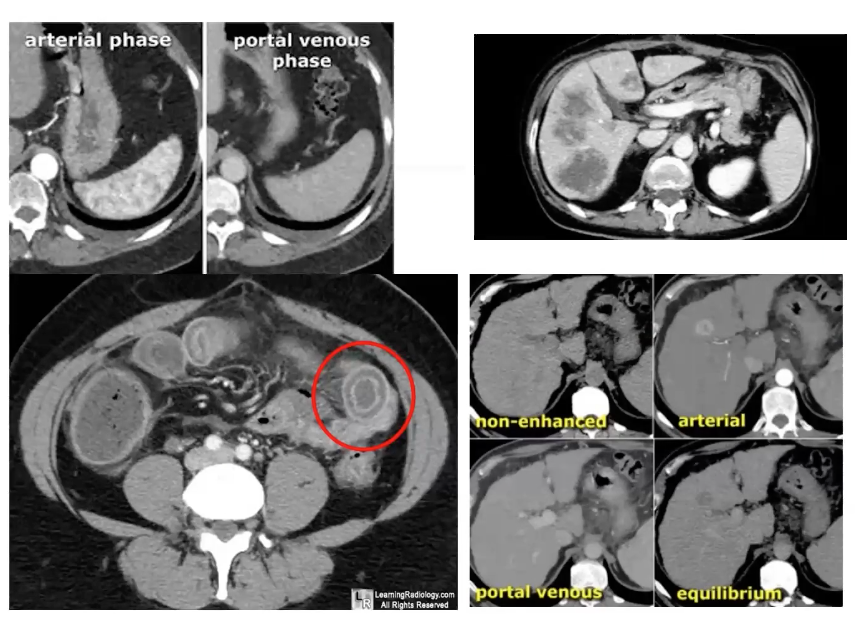

Adequate blood flow where the yellow arrows are and inadequate blood flow where the red arrows are

Different phase of contrast